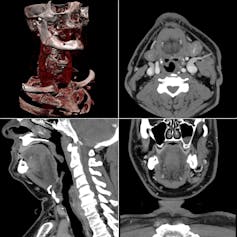

Por ejemplo, en el ámbito de la detección temprana de cáncer, una tarea podría ser que el algoritmo, al analizar una prueba de diagnóstico por imagen (TAC, ecografía, resonancia magnética, radiografía) conjuntamente con datos del paciente (demográficos, precedentes médicos, historial familiar, etc.), sea capaz de indicar si se trata de un tumor potencialmente maligno o no.

Para ello, en la fase de entrenamiento, se le muestra el conjunto de datos y pruebas diagnósticas de diferentes pacientes indicando en cada caso de qué tipo de tumoración se trata.

De esta forma, debería ser capaz, una vez entrenado, de identificar aquellos parámetros, tanto del historial como de las imágenes diagnósticas, que apuntan hacia una patología. Uno de los factores clave es que el algoritmo se haya entrenado con un amplio abanico de casuísticas.